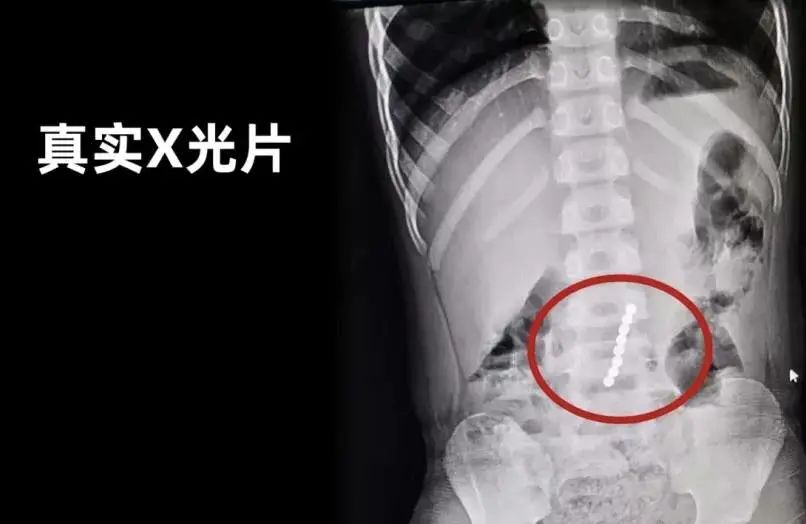

專(zhuān)家介紹,如果兒童吞食兩個(gè)及兩個(gè)以上的強(qiáng)力磁鐵,或者吞食強(qiáng)力磁鐵和其他磁性物體(鐵、鈷、鎳),磁鐵會(huì)在消化系統(tǒng)中與另一個(gè)磁鐵(或鐵磁性物體)吸附,并對(duì)腸壁產(chǎn)生壓力。

簡(jiǎn)要說(shuō),就是磁力珠磁力強(qiáng)大,即使隔著腸道也能黏在一起,影響腸胃的正常蠕動(dòng),甚至擠壓黏膜,導(dǎo)致黏膜缺血,嚴(yán)重時(shí)可能會(huì)造成腸梗阻,腸穿孔等。如果不小心誤食或者塞入體內(nèi),想要取出來(lái)有的需要緊急做腸鏡,有的則只能做開(kāi)腹手術(shù)!

此前曾有一則新聞:年僅1歲的洋洋肚子不知道吃了什么,肚子像炸了的氣球一樣。檢查發(fā)現(xiàn)洋洋是明顯的腸梗阻,醫(yī)生通過(guò)手術(shù)從洋洋身體內(nèi)取出如鴿子蛋大小般的水寶寶。